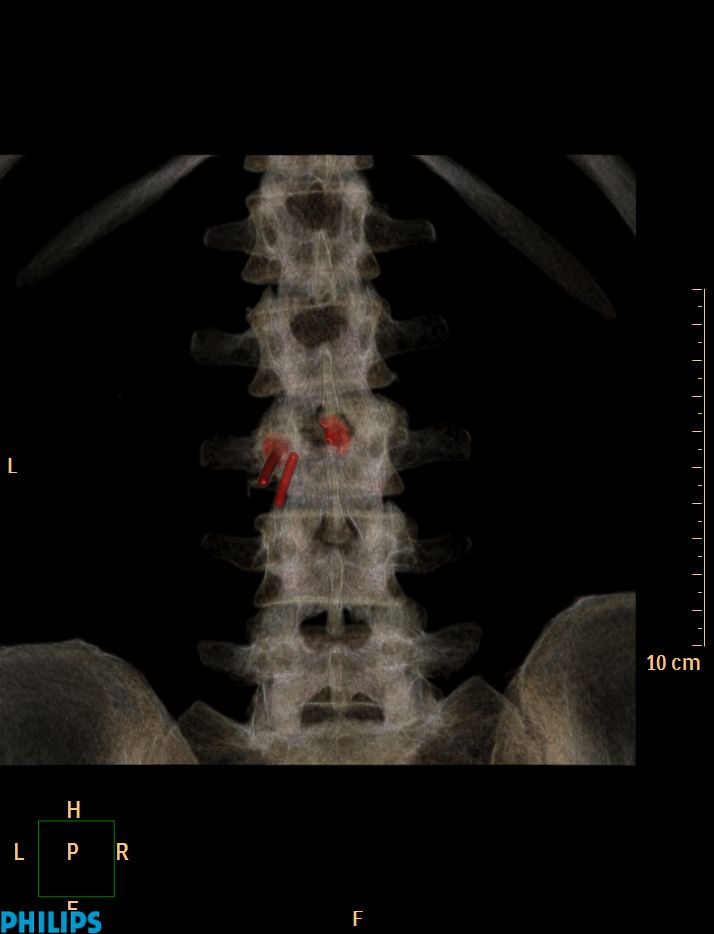

La vertébroplastie C'est ça d'attendre trop avant de retirer le trocard !!!